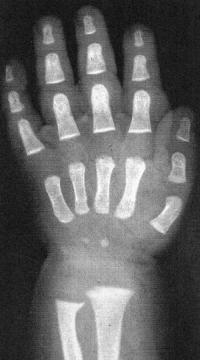

Sexo Feminino

Recém-Nascido

3 meses